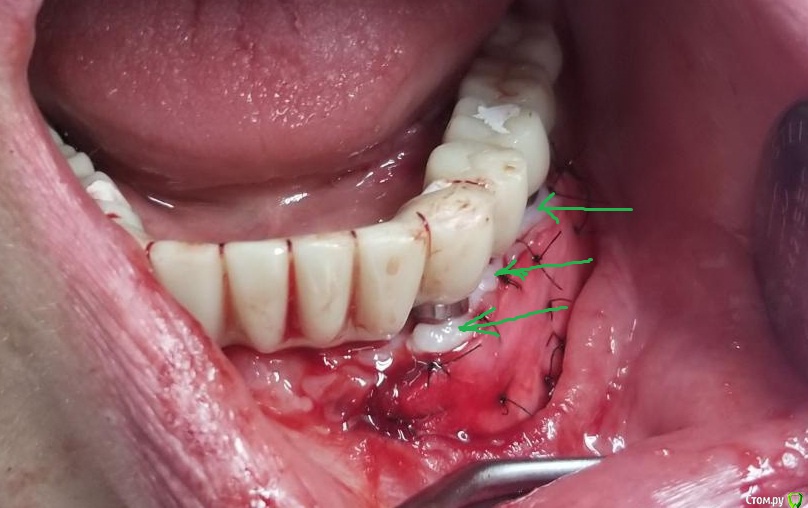

Kostoprav Опубликовано 14 июня, 2019 Поделиться Опубликовано 14 июня, 2019 Ксено+ауто +i prf, поверх титановых мембран перикард. кт через 5 мес.при и создании прикрепленки использовалась свиная дерма отечественного производителя 4 Ссылка на комментарий

Kostoprav Опубликовано 17 июня, 2019 Автор Поделиться Опубликовано 17 июня, 2019 спасибо за кейс подскажите то это что это.jpgсвоя прикрепленная слизистая 1 Ссылка на комментарий

Neilrus Опубликовано 20 июня, 2019 Поделиться Опубликовано 20 июня, 2019 а есть фото после снятия швов со свиной кожи? Как она выглядит после приживления, цвет, текстура Ссылка на комментарий

Kostoprav Опубликовано 20 июня, 2019 Автор Поделиться Опубликовано 20 июня, 2019 фото после выложу чуть позже после того как все заживет насчет комбустиологов не думаю что они ее используют поскольку продается небольшими кусочками Ссылка на комментарий